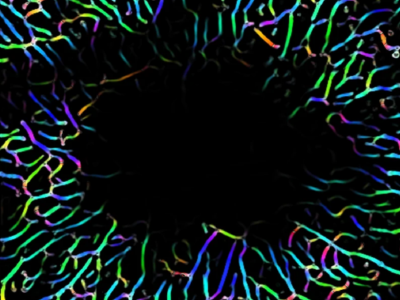

No 2 | La matière blanche classée